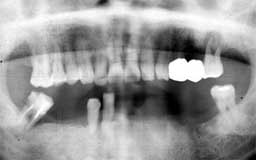

Qさん 初診時 55歳 男性

上顎の歯もかなり末期状態で、このまま放置しておくと下顎同様数年後には全ての歯を失う であろうことが予想されます

歯科治療

Qさん 11年後 66歳

今となっては古いタイプのインプラントですが、残存する下顎歯を最大限に利用してフルマ ウスの補綴処置を行いました。術後のメインテナンスは熱心で追加処置がないまま良好な予 後を保っています。10年間インプラントが機能していることも値打ちですが、何よりも上顎 の歯が1本も失われることなく機能していることに注目してください